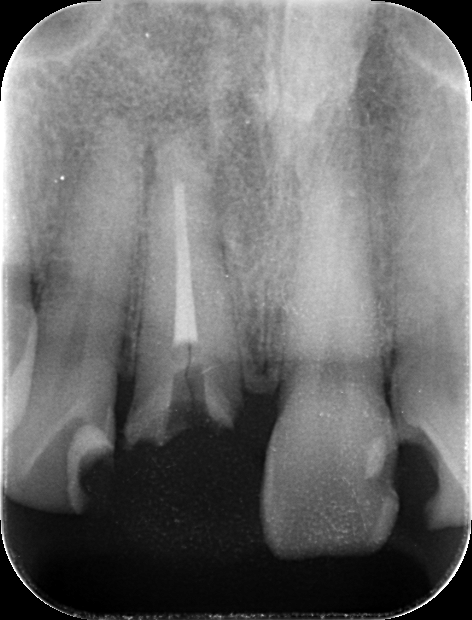

前歯が腫れてしまったと来院された患者様です。

レントゲンを見てみると歯根(歯の根の部分)が黒く溶けていることが分かり、抜歯と診断しました。

前歯のインプラントはとても難しく技術がないと歯茎が下がってしまったりと不具合が出てしまいます。

X-ray

処置後、非常に審美的な補綴物が入ったことが分かるかと思います。